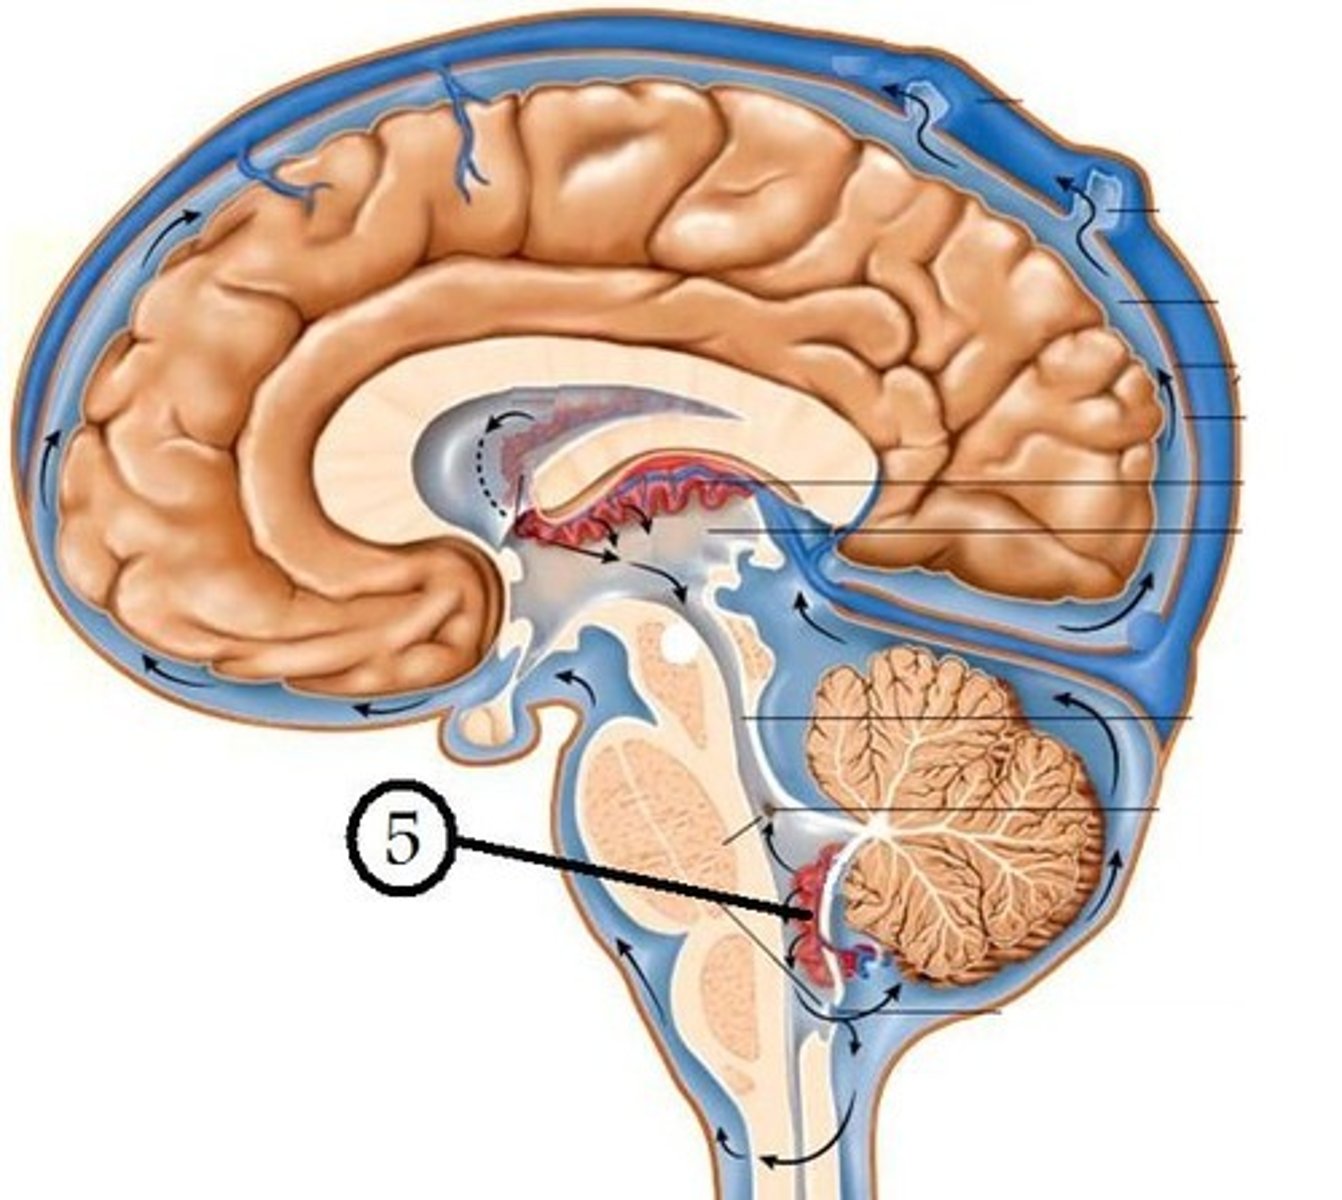

inferior medullary velum

structure attached to the ventral surface of the inferior medullary velum in the 4th ventricle that helps form CSF

choroid plexus

opening in the caudal aspect of the inferior medullary velum that allows CSF from the 4th ventricle to flow into the cisterna magna of the subarachnoid space

foramen of Magendie (or median aperture)

inferior cerebellar peduncles and choroid plexus

foramen of von Luschka (or lateral apertures)